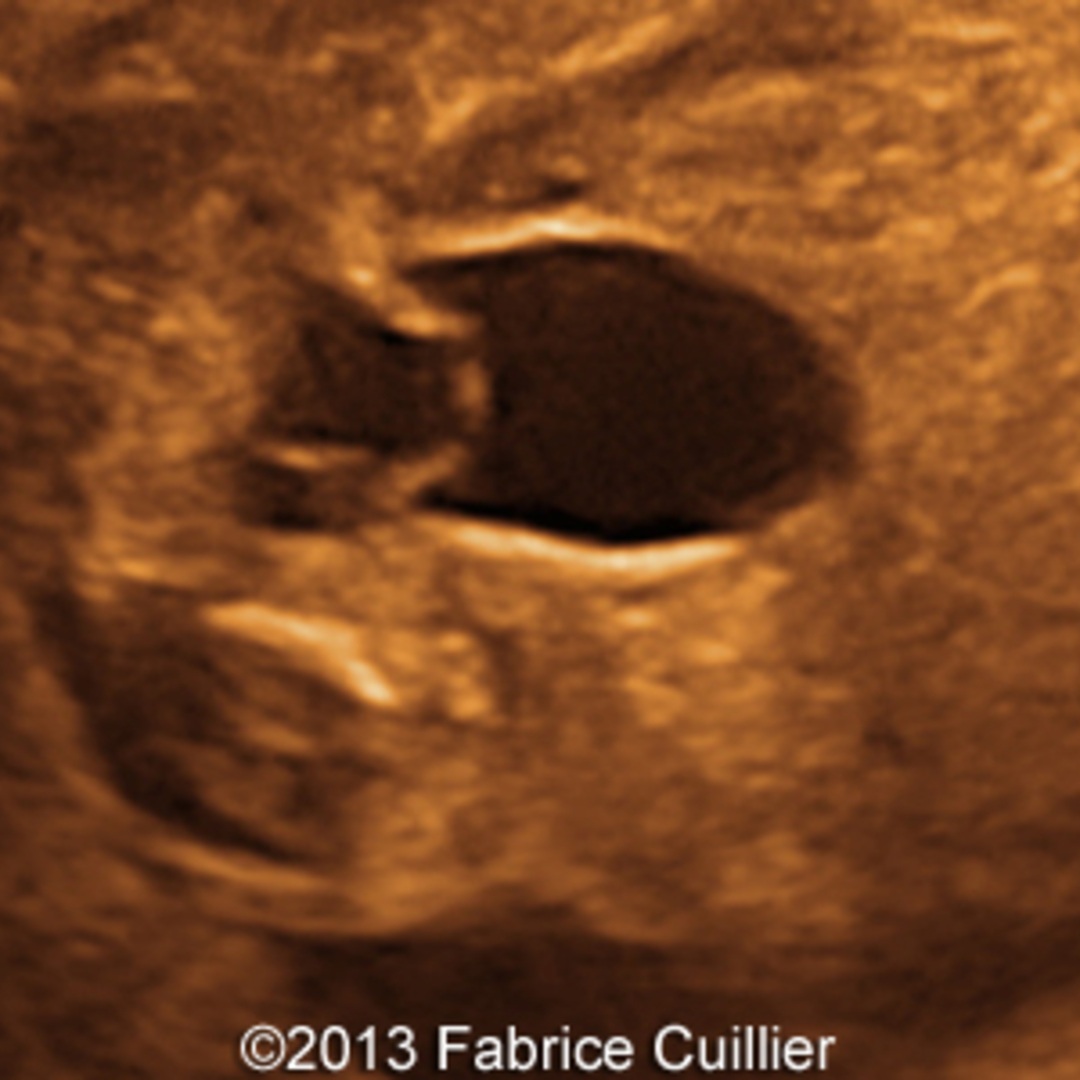

IVU-shows Adder head appearance or Cobra head appearance. Cystoscopy-shows translucent cyst which is thin walled surrounding ureteric orifice